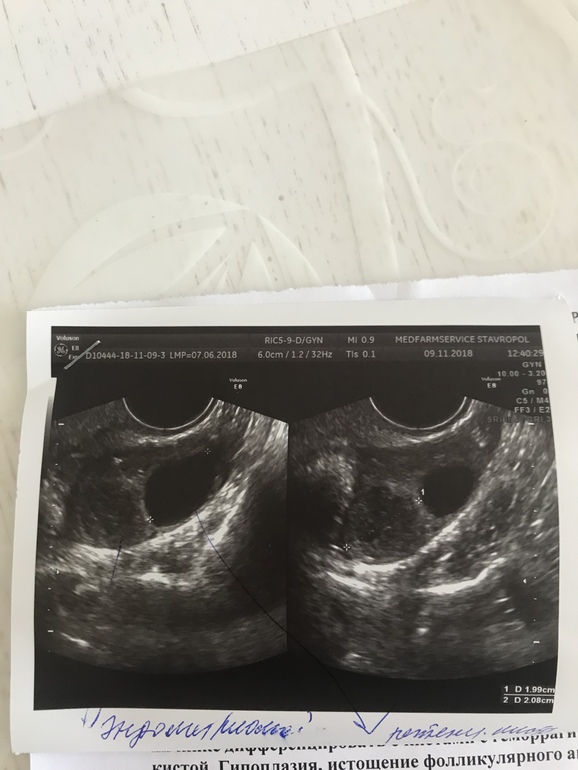

На УЗИ мне сказали: в правом яичнике 5 мелких фоликов, но тоже как бы под сомнением и что у меня там снова киста эндометриодная и ретенционная я в шоке! Теперь сижу и думаю ... не могла она чего напутать узистка ?! Она уверяла меня, что после визанны овуляция вообще не возможна..а я как ту почитала, что у многих сразу после отмены визанны она была и даже девочки...Помогите советом кто может, кто разбирается в снимках УЗИ ....

одна киста ушла (я все же думаю, что это фолик был), а другая уменьшилась с 23 мм до 15 мм и поэтому она сказала, что точно не эндометриодная)